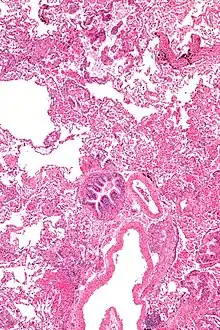

Pathology

Grossly, LAM lungs are enlarged and diffusely cystic, with dilated air spaces as large as several centimeters in diameter.[106][107] Microscopic examination of the lung reveals foci of smooth muscle-like cell infiltration of the lung parenchyma, airways, lymphatics, and blood vessels associated with areas of thin-walled cystic change. LAM lesions often contain an abundance of lymphatic channels, forming an anastomosing meshwork of slit-like spaces lined by endothelial cells. LAM cells generally expand interstitial spaces without violating tissue planes but have been observed to invade the airways, the pulmonary artery, the diaphragm, aorta, and retroperitoneal fat, to destroy bronchial cartilage and arteriolar walls, and to occlude the lumen of pulmonary arterioles.[106]

There are two major cell morphologies in the LAM lesion: small spindle-shaped cells and cuboidal epithelioid cells.[108] LAM cells stain positively for smooth muscle actin, vimentin, desmin, and, often, estrogen and progesterone receptors. The cuboidal cells within LAM lesions also react with a monoclonal antibody called HMB-45, developed against the premelanosomal protein gp100, an enzyme in the melanogenesis pathway.[108] This immunohistochemical marker is very useful diagnostically, because other smooth muscle-predominant lesions in the lung do not react with the antibody.[109] The spindle-shaped cells of the LAM lesion are more frequently proliferating cell nuclear antigen positive than the cuboidal cells, consistent with a proliferative phenotype.[108] Compared with cigar-shaped normal smooth muscle cells, spindle-shaped LAM cells contain less abundant cytoplasm and are less eosinophilic. Estrogen and progesterone receptors are also present in LAM lesions,[110][111][112] but not in adjacent normal lung tissue.[113] LAM lesions express lymphatic markers LYVE-1, PROX1, podoplanin and VEGFR-3. The smooth muscle-like cells of AMLs are morphologically and immunohistochemically similar to LAM cells, including reactivity with antibodies directed against actin, desmin, vimentin, and HMB-45 as well as estrogen and progesterone receptors.[114][115] Unlike the dilated airspaces in emphysema, the cystic spaces found in LAM may be partially lined with hyperplastic type II cells.[116]